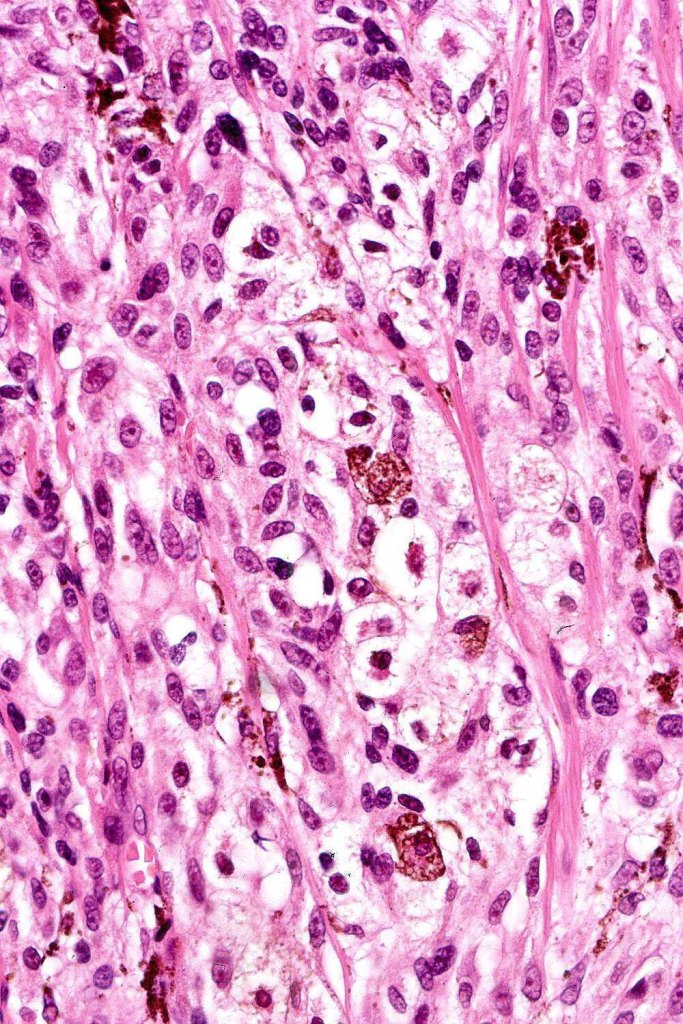

•Symmetrical, circumscribed wedge-shaped infiltrate-most common growth pattern with the broad base uppermost, deeper aspect extends along appendageal structures & neurovascular bundles with a fasciular or plexiform pattern

•Deep spindle cells

•Focal atypia (enlarged, hyperchromatic nuclei)

•Melanophages

•Occasional mitoses

. Perineural spread sometimes seen, infiltration of arrector pili muscles common

Atypical features which may be encountered include marked nuclear pleomorphism, conspicuous mitotic activity, atypical mitoses (atypical or borderline lesion)- may be associated with lymph node involvement although frank maliganncy is exceptional